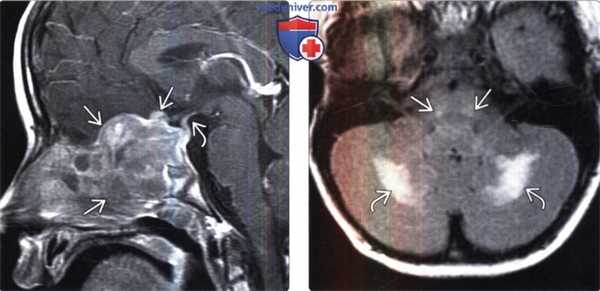

(Слева) МРТ, постконтрастное Т1-ВИ, режим подавления сигнала от жира, сагиттальный срез: у пятилетнего мальчика с хроническими головными болями и несахарными диабетом определяется гетерогенно накапливающее контрастное вещество поражение центральных отделов основания черепа. Обратите внимание на утолщение и смещение воронки гипофиза.

(Справа) МРТ, FLAIR, аксиальный срез: у шестилетнего мальчика с нарушением поведения, в белом веществе мозжечка определяются сливные гиперинтенсивные зоны демиелинизации. Обратите внимание на вовлечение в процесс ядер отводящих нервов.